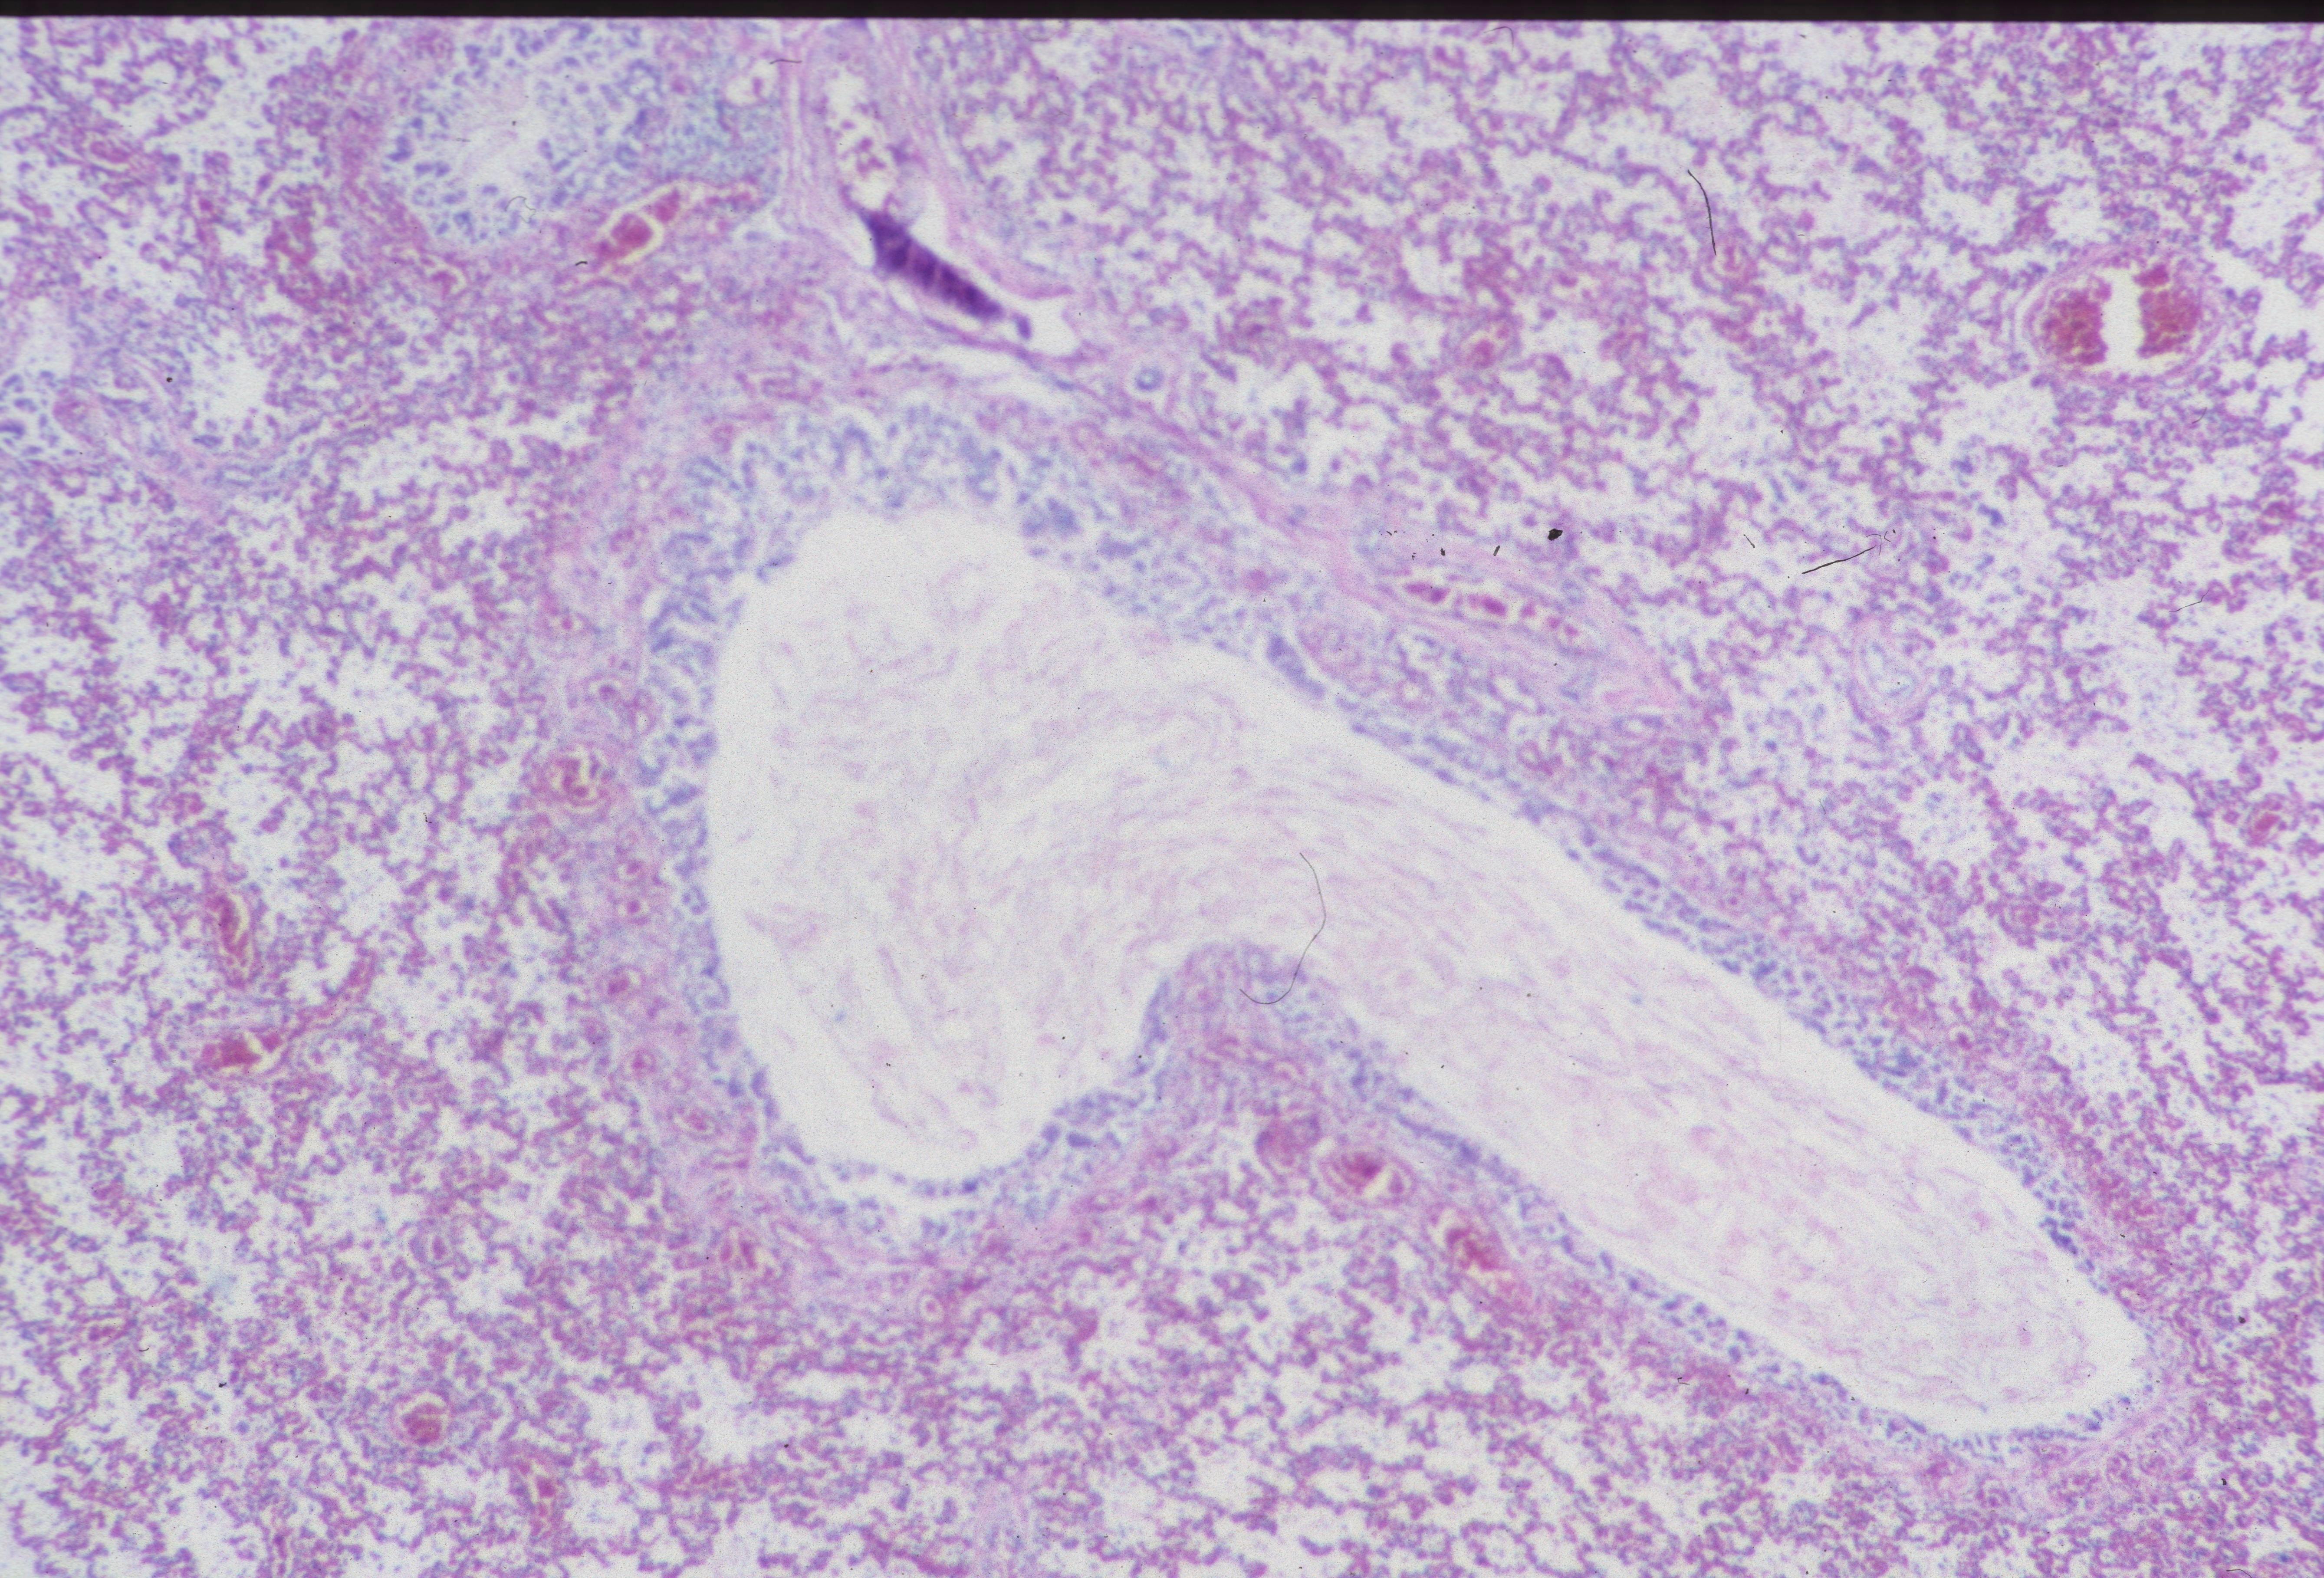

Distal airway expansion: The lung in the fetus is naturally in the unexpanded state. With respiratory effort, even in fluid, there may be some expansion of the air passage. A complicating postmortem event is focal expansion of airways with gas (Fig 25).

This gas is presumed to be from bacterial action in the lung, usually with no evidence of inflammation. The importance of this phenomenon is that it not be mistaken for postnatal respiration in a stillborn fetus not born in the hospital with the forensic inference that respiration had occurred and death was after delivery.